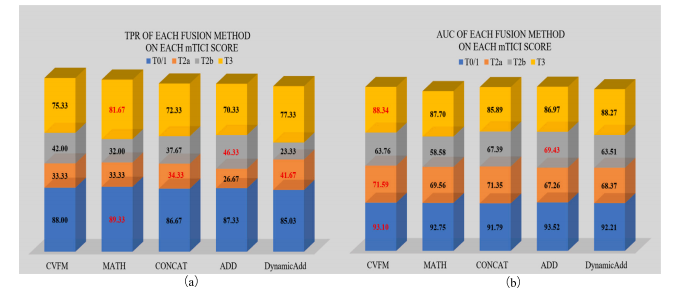

Fig. 6. TPR (a) and AUC (b) of different fusion methods on each mTICI score of AmTICIS. The best results are indicated in red.

图6:(a)不同融合方法在自动改良脑梗死溶栓分级评分(AmTICIS)数据集每个mTICI评分等级上的真阳性率(TPR);(b)不同融合方法在AmTICIS数据集每个mTICI评分等级上的曲线下面积(AUC)。最优结果以红色标出。

We proposed a CVFSNet based on dual-view angiographic imagesfor automatic, objective, end-to-end mTICI scoring and built a crossview fusion module, CVFM, to integrate, aggregate, and complementfeatures from different views. In the ablation experiments, we firstcompared the performance between single-view and dual-view inputs,demonstrating the necessity of dual-view image input. This may bedue to the fact that DSA imaging is projection-compressed and intracranial vessel structures are complex, leading to vessel overlap insingle-view images, which affects the model’s ability to characterizeblood flow accurately. Then, by comparing different methods of dualview feature fusion, we verified the effectiveness of the CVFM module.CVFM leverages prior positional knowledge of coronal and sagittalviews, constructs oblique sagittal features using trigonometric functionsand the Pythagorean theorem, and employs a transformer-like moduleto explore complementary relationships between coronal and sagittalfeatures, thereby building global dependencies and generating more expressive fused features, ultimately enhancing performance. In the comparative experiments, we compared our approach with some classicaland state-of-the-art video feature classification models, demonstratingsuperior performance andgood stability.In the dichotomized experiments, CVFSNet demonstrated performance exceeding 90% across all indicators, implying that CVFSNet mayhave the potential for clinical application in determining the adequacyof mTICI scores. However, our study also has limitations. Firstly, thesevideo feature classification methods that were compared in the comparative experiments only supported single-view inputs, which maydisadvantage their comparison in terms of performance. Additionally,the AmTICIS dataset constructed in this study only includes data forM1 segment stenosis, limiting its clinical applicability. In the future,we plan to expand the dataset to include more mTICI scoring datawith various vessel stenosis, such as Internal Carotid Artery (ICA), BaseArtery (BA), Anterior Cerebral Artery (ACA), and Posterior CerebralArtery (PCA) etc., thereby constructing a more comprehensive scoringdataset. Also, the sample size of AmTICIS can be further expanded byincorporating data from multiple centers to enhance its diversity.In conclusion, we propose a novel CVFSNet in this paper for automatic, objective, and end-to-end mTICI scoring. Specifically, CVFSNetemploys dual branches to simultaneously extract spatial–temporal features from coronal view and sagittal view, and these cross-view featuresare fused through a novel cross view fusion module that explores thepositional characteristics of coronal and sagittal views to fuse andgenerate a pseudo-oblique sagittal feature and deploys a transformerlike architecture to explore the correlation between different viewfeatures, ultimately constructing more representative features to enhance the scoring performance of the model. In addition, we providea newly collected and the first publicly available digital subtractionangiography image dataset with expert annotations (AmTICIS) for automatic mTICI scoring, which can effectively promote researchers toconduct studies of ischemic stroke based on DSA images and finallyhelp patients get better medical treatment. Extensive experimentationresults demonstrate the promising performance of our methods and theeffectiveness of the cross-view fusion module.

我们基于双视角血管造影图像提出了CVFSNet网络,用于实现自动、客观、端到端的脑梗死溶栓治疗改良分级(mTICI)评分,并构建了一个跨视角融合模块(CVFM),以整合、聚合和补充来自不同视角的特征。在消融实验中,我们首先比较了单视角输入和双视角输入的性能,结果表明了双视角图像输入的必要性。这可能是因为数字减影血管造影(DSA)成像是投影压缩的,且颅内血管结构复杂,导致单视角图像中出现血管重叠,从而影响了模型准确表征血流的能力。然后,通过比较不同的双视角特征融合方法,我们验证了CVFM模块的有效性。CVFM利用冠状面和矢状面的先验位置知识,使用三角函数和勾股定理构建斜矢状面特征,并采用类似Transformer的模块来探索冠状面和矢状面特征之间的互补关系,从而建立全局依赖关系,并生成更具表现力的融合特征,最终提升性能。在对比实验中,我们将我们的方法与一些经典的以及最先进的视频特征分类模型进行了比较,结果显示出我们的方法具有优越的性能和良好的稳定性。 在二分类实验中,CVFSNet在所有指标上的表现均超过了90%,这意味着CVFSNet在确定mTICI评分是否足够方面可能具有临床应用潜力。然而,我们的研究也存在局限性。首先,在对比实验中所比较的这些视频特征分类方法仅支持单视角输入,这在性能比较方面可能对它们不利。此外,本研究构建的AmTICIS数据集仅包含大脑中动脉M1段狭窄的数据,限制了其临床适用性。未来,我们计划扩展该数据集,纳入更多具有各种血管狭窄情况的mTICI评分数据,例如颈内动脉(ICA)、基底动脉(BA)、大脑前动脉(ACA)和大脑后动脉(PCA)等,从而构建一个更全面的评分数据集。同时,通过纳入多个中心的数据来进一步扩大AmTICIS的样本量,以提高其多样性。 总之,本文提出了一种新颖的CVFSNet网络,用于自动、客观、端到端的mTICI评分。具体而言,CVFSNet采用双分支同时从冠状面和矢状面提取时空特征,并且这些跨视角特征通过一个新颖的跨视角融合模块进行融合。该模块探索冠状面和矢状面的位置特征,以融合并生成伪斜矢状面特征,并部署了类似Transformer的架构来探索不同视角特征之间的相关性,最终构建出更具代表性的特征,以提升模型的评分性能。此外,我们提供了一个新收集的、首个带有专家注释的公开可用的数字减影血管造影图像数据集(AmTICIS),用于自动mTICI评分,这可以有效地推动研究人员基于DSA图像开展缺血性中风的研究,并最终帮助患者获得更好的治疗。大量的实验结果证明了我们方法的良好性能以及跨视角融合模块的有效性。

Table 3Performance of different fusion methods on CVFSNet scoring performance on AmTICIS. Best results are indicated in bold.

表3:在自动改良脑梗死溶栓分级评分(AmTICIS)数据集上,不同融合方法对跨视图融合评分网络(CVFSNet)评分性能的影响。最优结果以粗体显示。